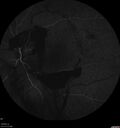

44 year old man About 2 months ago, the patient went to the beach with his family and noticed a hair in the eye sight in the left eye.  He was trying to rinse it out and saw that there was something not right.  He googled the problem and there was something about a floater and not being a big deal.  His vision was pretty good.  He was not getting regular eye examinations.  He did get checked in 2015 and got new glasses.  He had not been back since then for the last 5 years except for glasses. Last week the vision in the left eye got bad.  The vision in the right eye is fine.   VA OD: sc20/40 PH20/25 NscJ2 VA OS: sc20/63-2 PH20/32-1 NscJ1 IOP: TP: OD:17 OS:19

Proliferative Diabetic Retinopathy and vitreous hemorrhage left eye330 views44 year old man with type II diabetes for 14 years and no eye examinations in the last 5 years. VA 20/40 right eye and 20/60 left eye. Vision loss has been for about a week in the left eye.00000

44 year old man About 2 months ago, the patient went to the beach with his family and noticed a hair in the eye sight in the left eye.  He was trying to rinse it out and saw that there was something not right.  He googled the problem and there was something about a floater and not being a big deal.  His vision was pretty good.  He was not getting regular eye examinations.  He did get checked in 2015 and got new glasses.  He had not been back since then for the last 5 years except for glasses. Last week the vision in the left eye got bad.  The vision in the right eye is fine.   VA OD: sc20/40 PH20/25 NscJ2 VA OS: sc20/63-2 PH20/32-1 NscJ1 IOP: TP: OD:17 OS:19Â